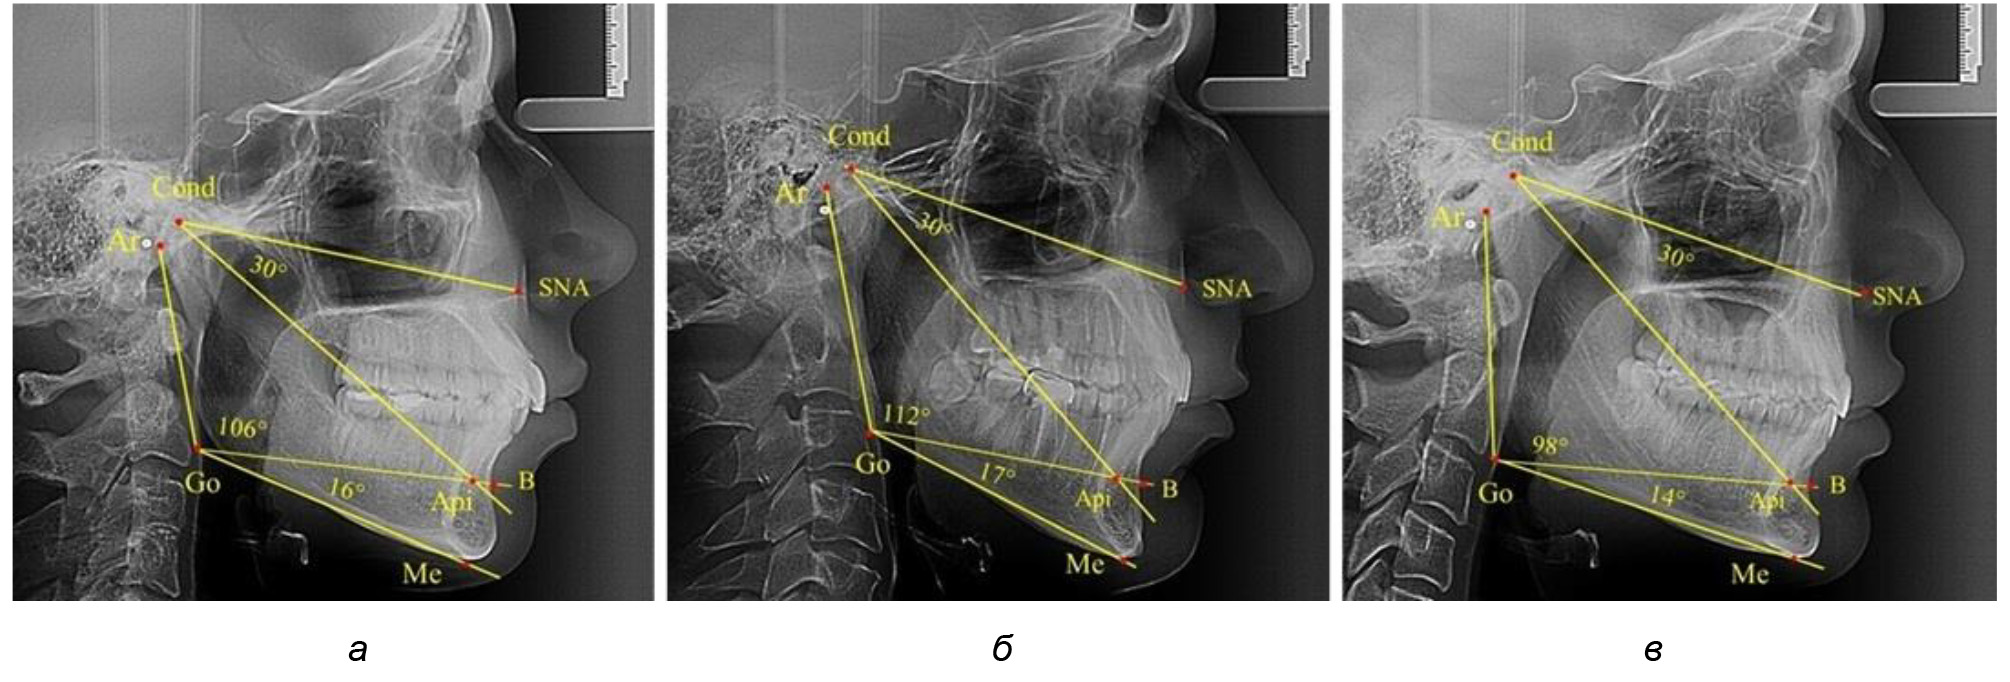

Для горизонтального типа роста было характерно достоверное р ˂ 0,05 уменьшение нижнечелюстного угла до (115,57 ± 0,56)°. Величина угла Ar-Go-Api составила (102,71 ± 1,62)°, а угол Api-Go-Me был (12,86 ± 0,74)° (рис. 3).

Рис. 3. Особенности ТРГ при нейтральном (а), вертикальном (б) и горизонтальном (в) типе угла нижней челюсти в постоянном прикусе

Таким образом, вне зависимости от величины нижнечелюстного угла, показатели угла гнатической части лица были в пределах 30°, что может расцениваться в качестве оптимального физиологического показателя параметров гнатической части лица. Анализ ТРГ проведен у 31 ребенка в различные периоды дентального онтогненеза, включая прикус молочных зубов и различные группы прорезывания постоянных зубов.